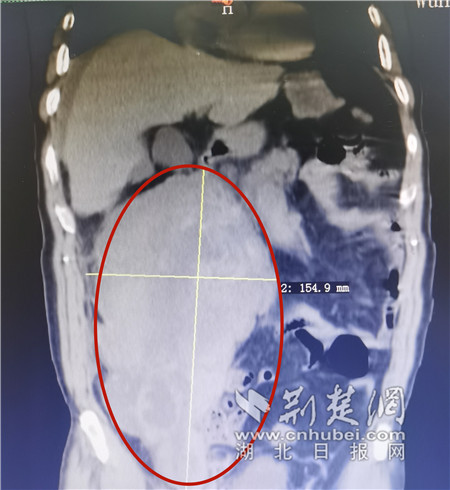

李先生腹腔内的血肿。通讯员供图

10月9日,57岁的李先生(化姓)莫名出现上腹痛3天,家人见状,赶紧将其送往了武汉市中心医院后湖院区检查,入院时,李先生就出现了休克的情况,经过医生的紧急救治才慢慢苏醒。该院后湖院区肝胆胰外科副主任医师郑小林为其进行细致检查发现,李先生的后腹膜部分有一巨大血肿,约有足球大小。“这种情况应该是血管出血所致,得赶紧找到出血点以及出血原因,否则后果不堪设想。”郑小林表示。

为了找到血肿原因,通过加强CT与肝动脉造影,该科专家团队发现其腹腔干、肠系膜上动脉均有夹层,形成了血管瘤。“我们高度怀疑,出血点可能这两处血管瘤所在的位置,但是造影结果显示,这两处都没有明显的渗漏。”郑小林说,这可能是间歇性出血后,血凝块堵住了出血点,短暂的阻止了血液流出,但通过这么大的血肿可以判断,渗漏已经有一段时间,虽然是间断性的,但一直没有停过。